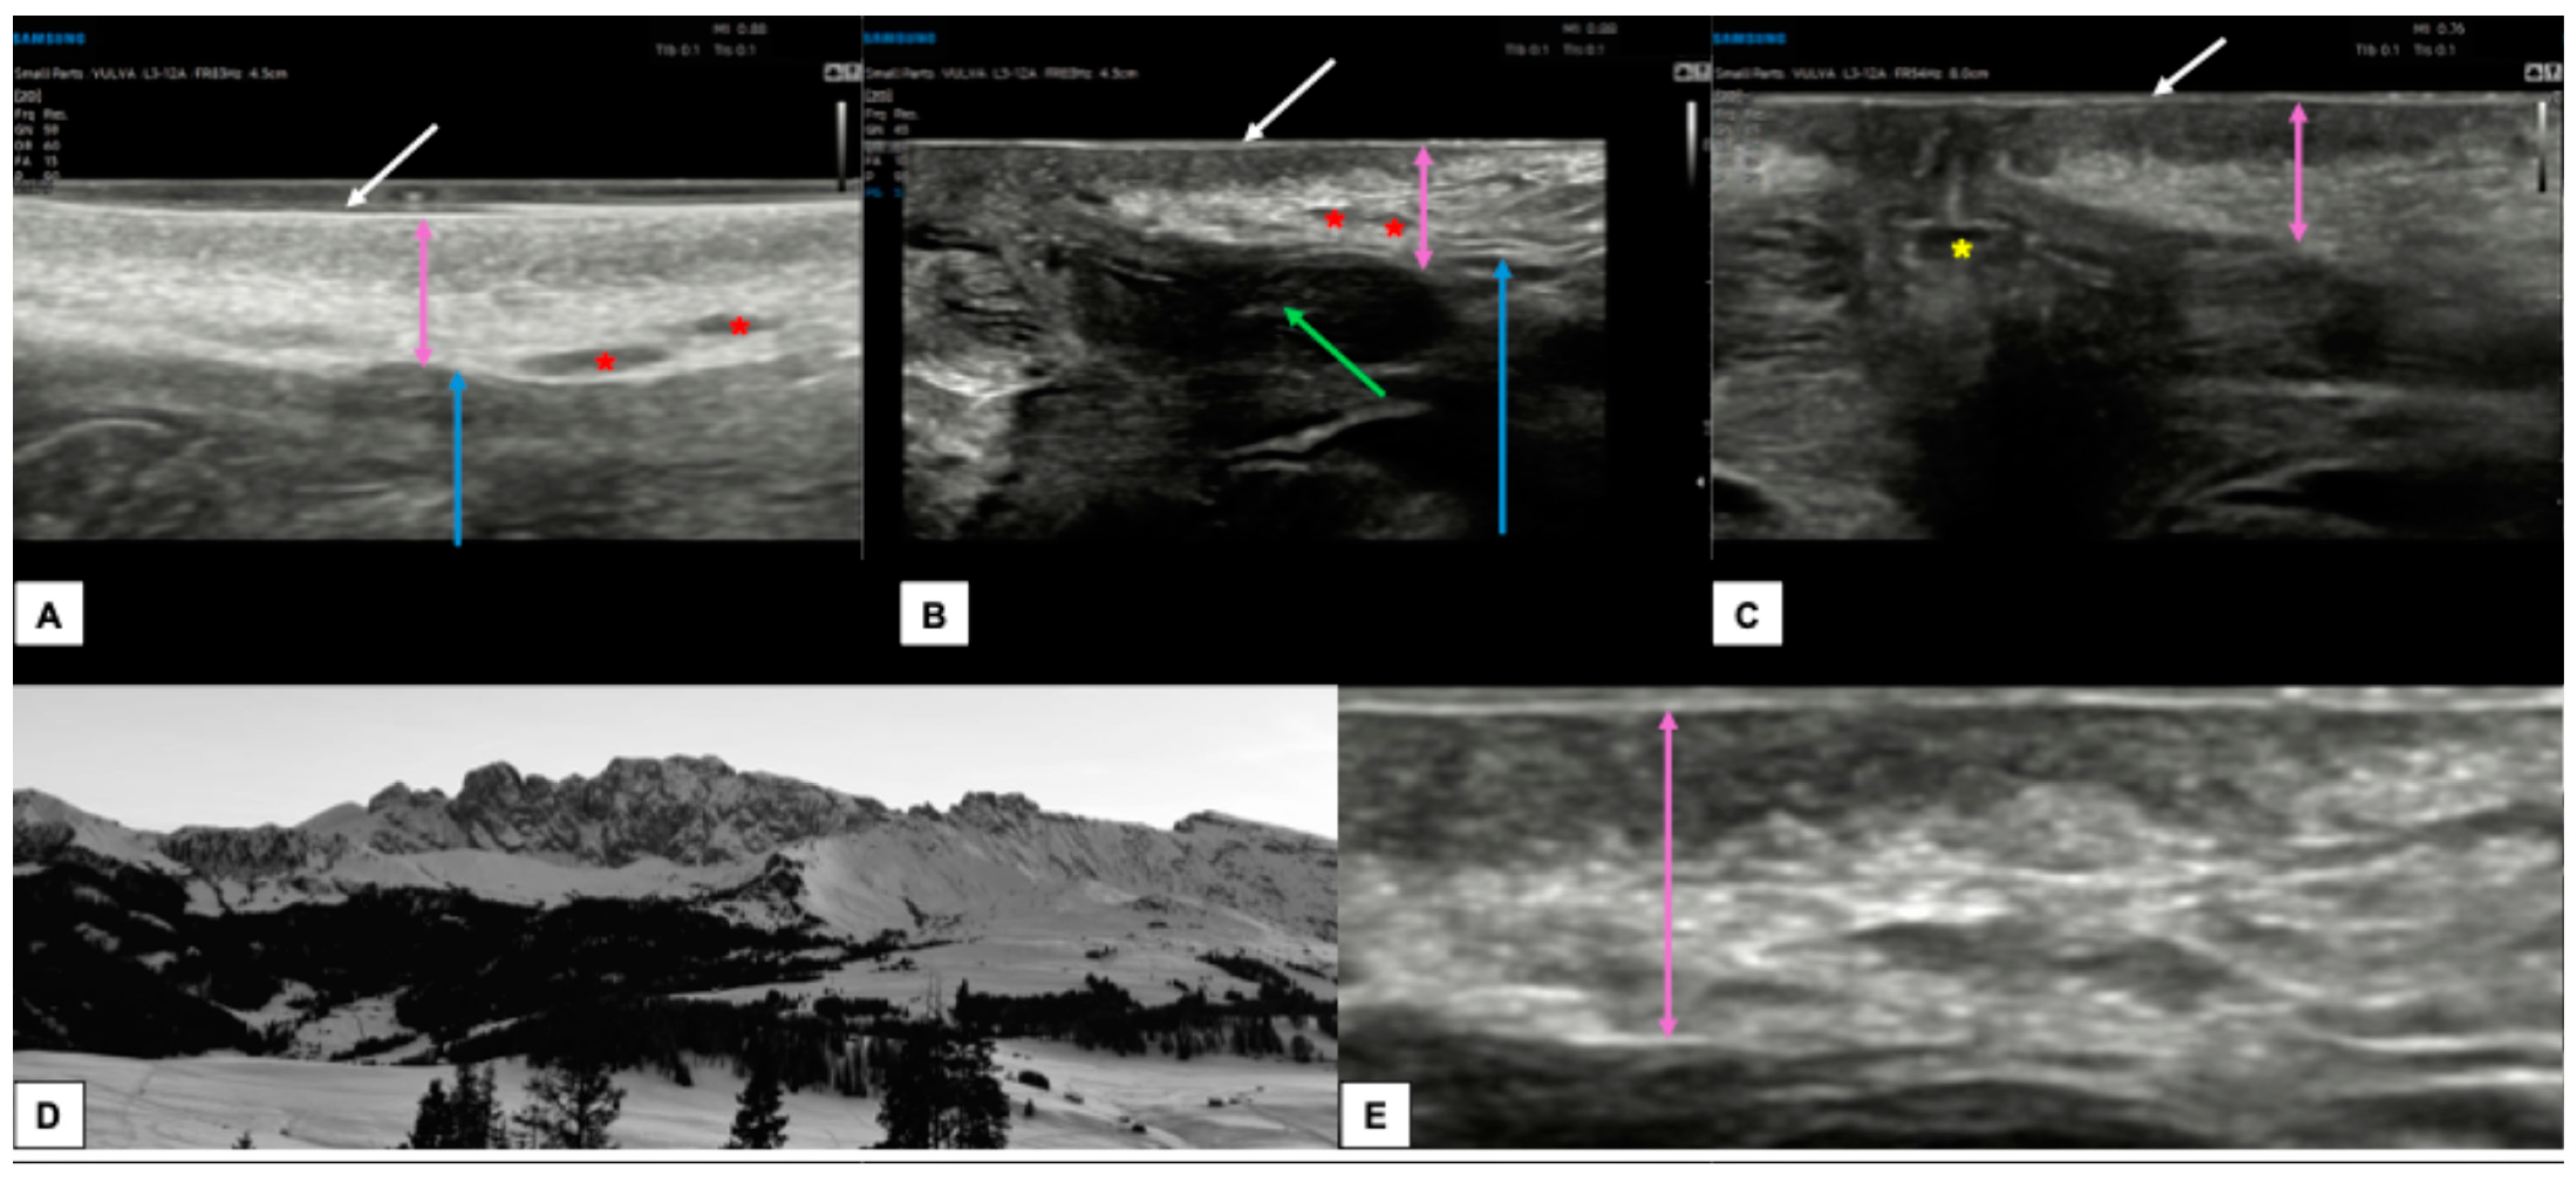

- The vulva should be virtually visualized as a clock face and divided into four quadrants according to the ISSVD nomenclature [14] by an imaginary vertical line that passes through the clitoris and the anus (defining the lateral sides—right and left) and a horizontal line from the upper border of the hymenal ring (defining the anterior and posterior portions) (Figure 3A). This allows the vulva to be studied in its entirety and to describe the location and extension of vulvar lesions accurately.

- The probe should be placed in a transverse position at the beginning of the examination, and the clitoral area should be assessed first. From here, the examination should continue clockwise to study the remaining areas (Figure 3B).

- Once the clockwise rotation is completed and the clitoral area is reached again, the probe should be placed longitudinally and, starting at the level of the vestibule, moved laterally, first one way and then the other, extending it to the outer edge of the labia majora (Figure 3C). During this phase, an additional amount of gel should be applied to increase the distance between labia minora and majora to distinguish the different layers better [4]. A linear probe, preferably > 15 mHz (HFUS), is recommended to achieve optimal skin layer stratification [15]. The physiological presence of pubic hairs can alter the sonographic image. For this reason, some authors indicated hair removal the day before the imaging is performed.